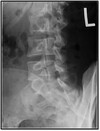

Q

What type of fracture is this?